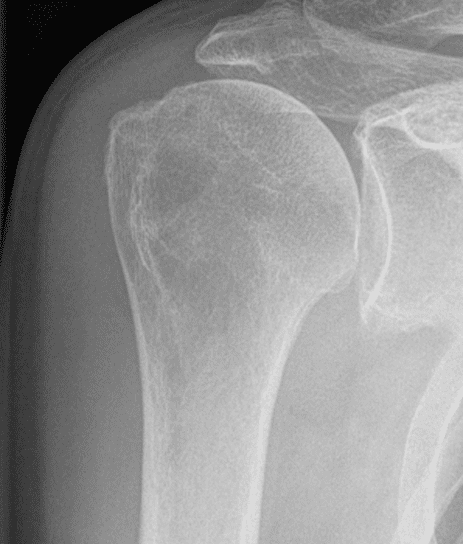

Patient Cases